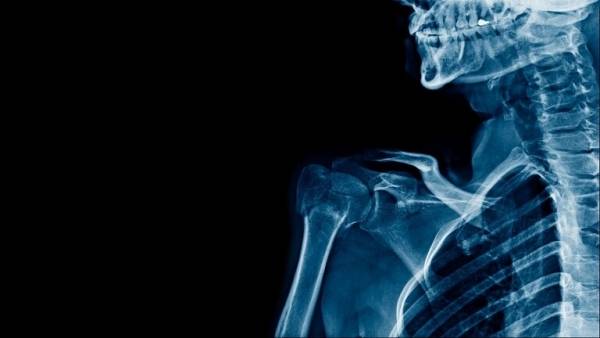

6 حقائق مفاجئة عن الهيكل العظمي البشري

غالبا ما يندهش الناس عندما يعلمون أن العظام هي نسيج حيوي، حيث ترمم نفسها استجابة للنشاط اليومي في عملية خلوية تُسمى "إعادة التصميم".

وفيما يلي بعض الحقائق الأخرى حول الهيكل العظمي: